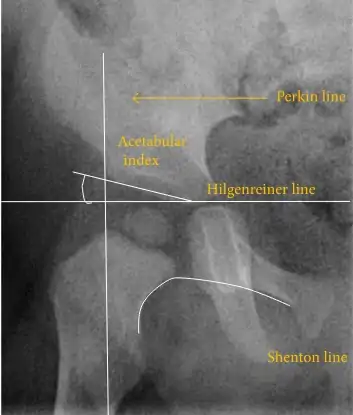

The most useful lines and angles that can be drawn in the pediatric pelvis assessing hip dysplasia are as follows:[45] Different measurements are used in adults.[45]